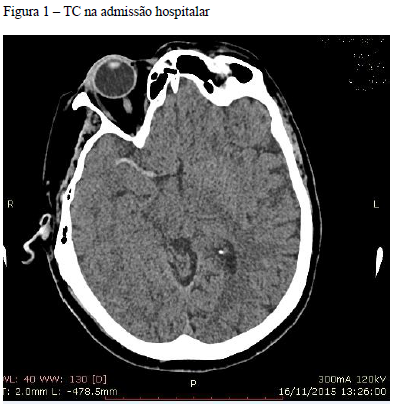

Mulher, 20 anos, é internada com náusea, vômitos, poliúria e polidipsia. HPP: diabética em tratamento irregular com insulina NPH.

Exames iniciais: glicose 402 mg%, Na 134 mEq/l, K 3,1 mEq/l, fosfato 3,2 mg%, creatinina 1,2 mg%, ureia 69 mg%, pH 7,18 e cetonúria ++. Cálculo do anion gap - aumentado.